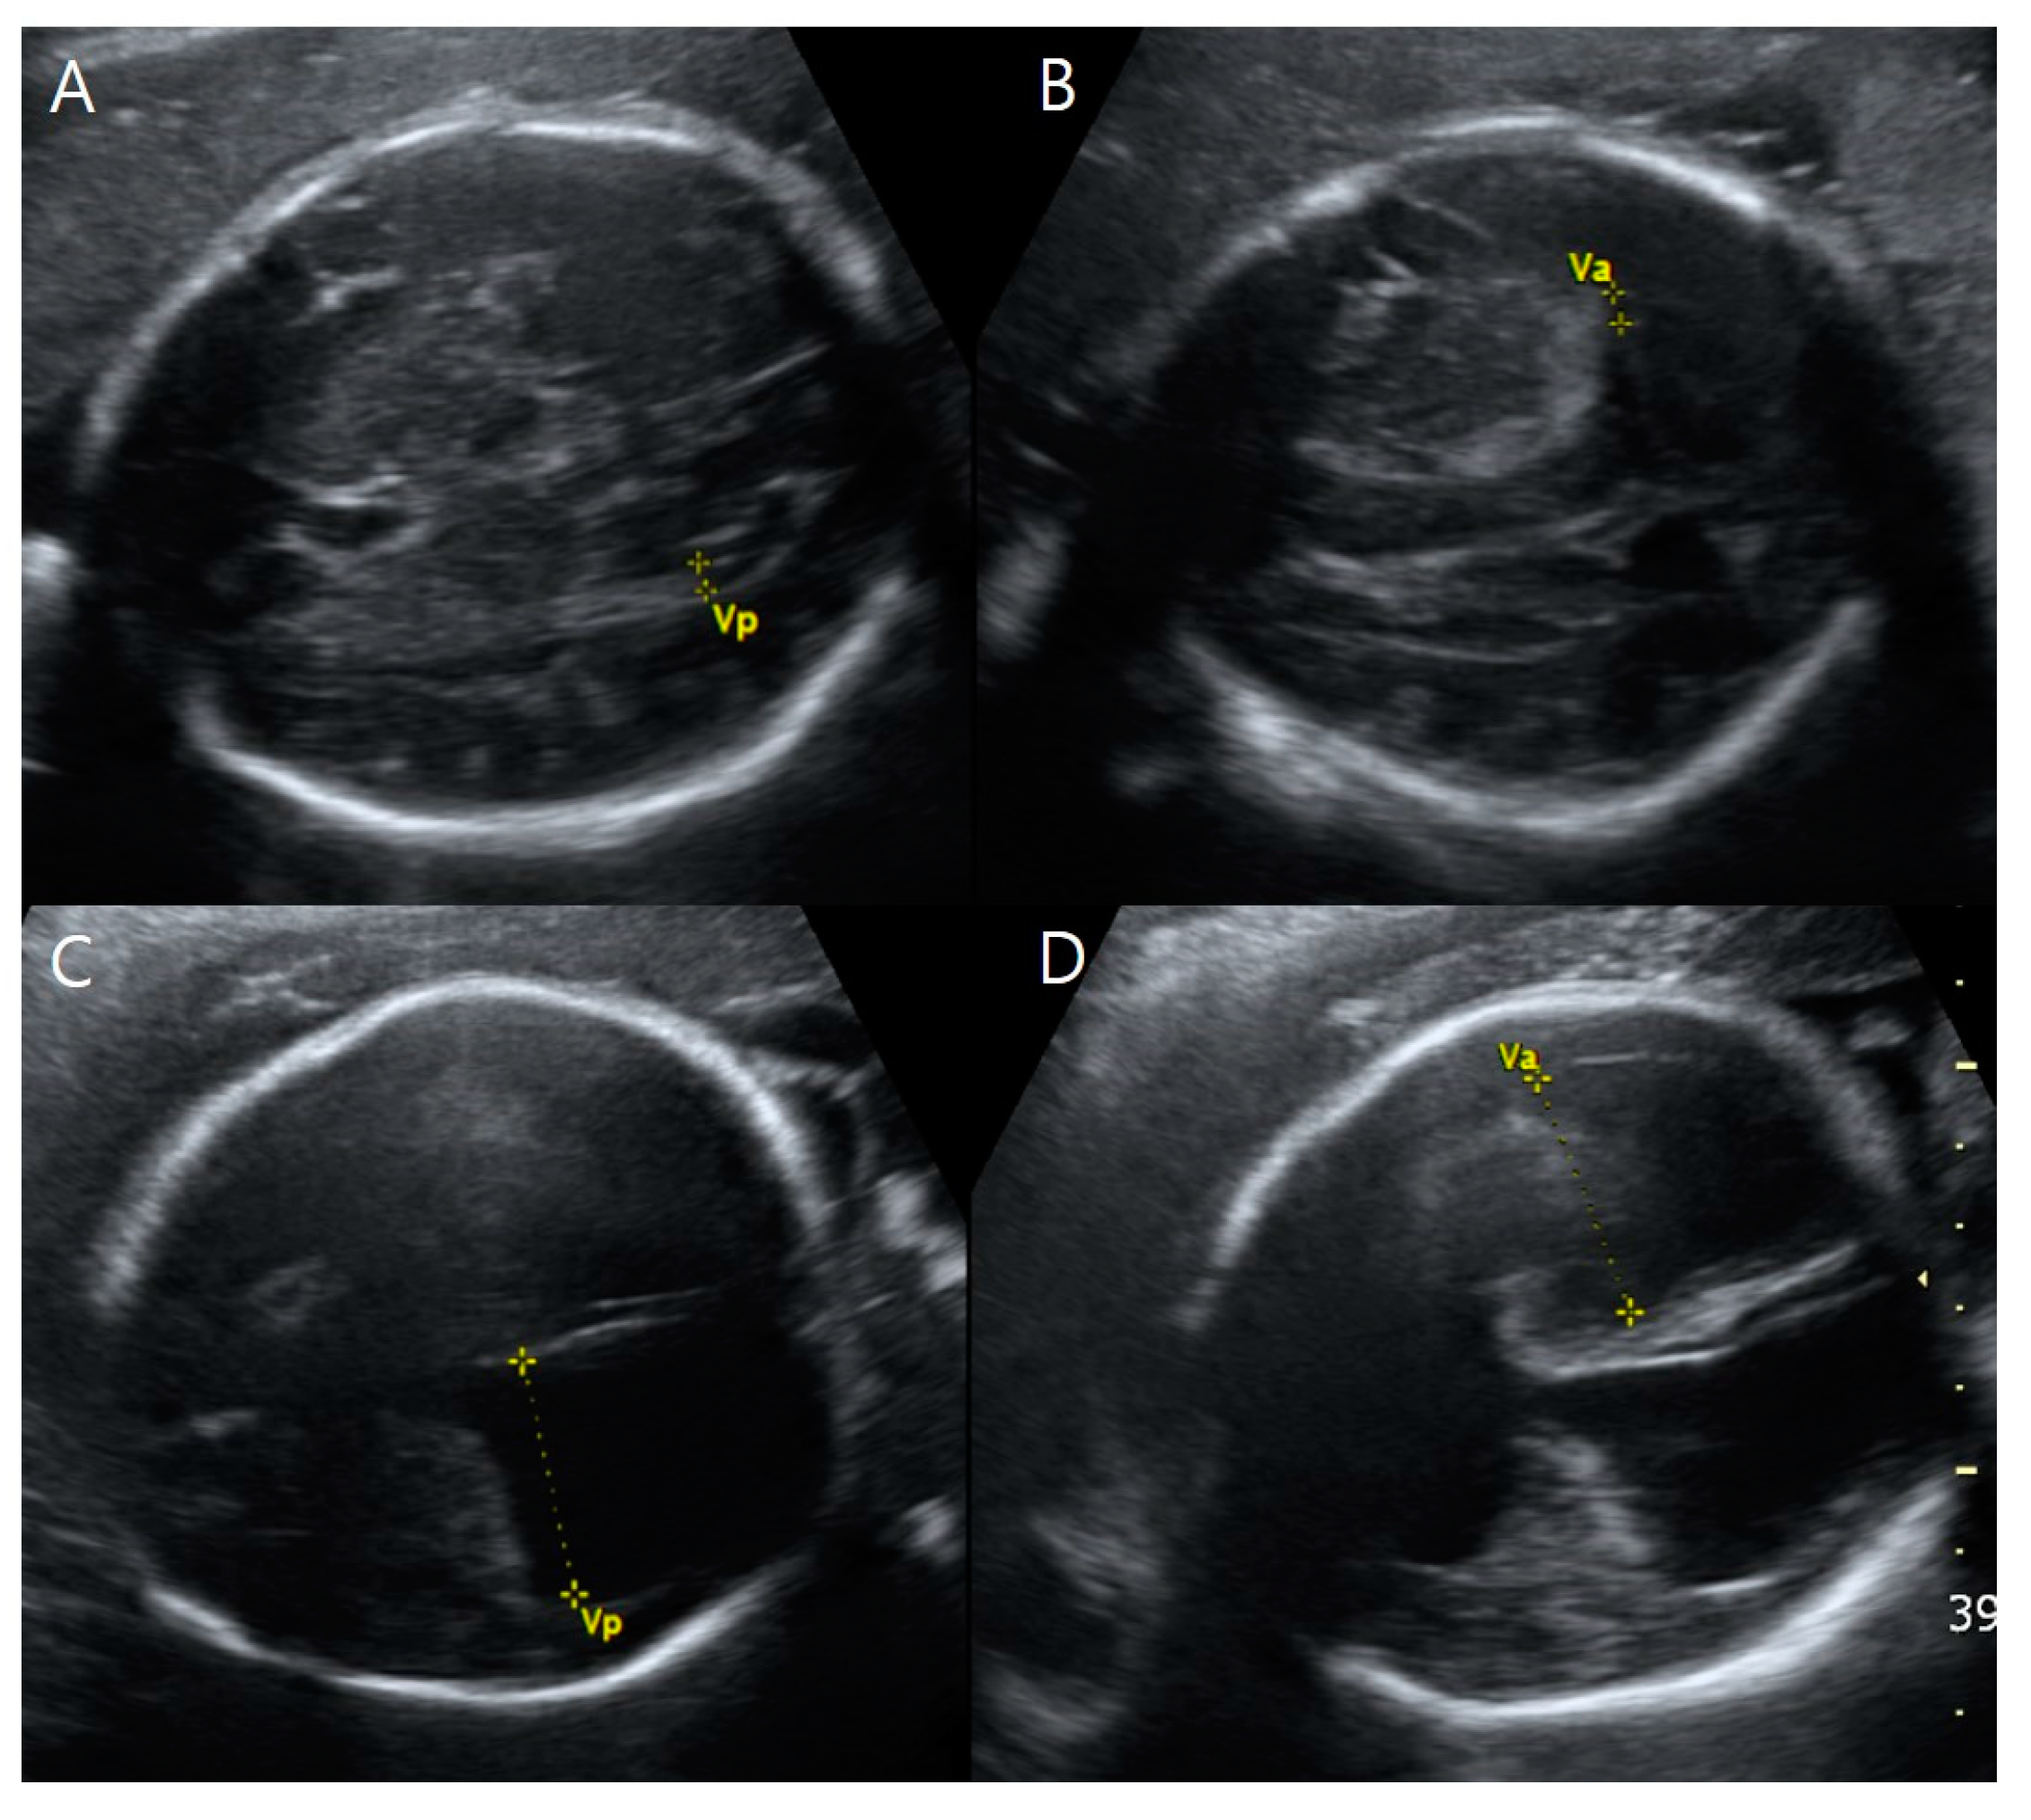

Targeted ultrasound examinations showed a dichorionic-diamniotic twin pregnancy with a definite discordance in estimated fetal weight (EFW) between the first (fetus A, male) and the second (fetus B, female) fetuses. The twins were highly suspected to be dizygotic because they are different sexes. The male fetus weighed 1203 g at 31 + 3 weeks gestation (10th percentile at 32 weeks’ gestation-1310 g), with the single-deepest pocket of amniotic fluid measuring 10 cm. The female twin weighed 1595 g at 31 + 3 weeks gestation, with the single-deepest pocket of amniotic fluid measuring 4 cm. The twins also showed discordance in structural abnormalities. Compared with fetus B, fetus A presented not only with hydrocephalus (Figure 1) but also bilateral dysplastic upper arms, radial aplasia (Figure 2), right pulmonary agenesis (Figure 3), interrupted inferior vena cava (IVC), a unilateral hypoplastic ectopic kidney (Figure 4), a single umbilical artery (Figure 5), a tracheoesophageal fistula with small stomach (Figure 6), polyhydramnios, and anal atresia (Figure 7).

On transventricular view, both of fetus A’s lateral ventricles were severely dilated at 31.0 mm and 29.5 mm, resulting in cortical mantle thinning (Figure 1). Fetus A’s third ventricle was dilated to 5.8 mm, but no other brain abnormalities were found.

Figure 1. Transventricular view of the twin fetuses on ultrasound examinations at 31 + 3 weeks gestation. (A,B) Fetus B, a healthy female with normal-sized atrial widths of both left and right lateral ventricles (Va and Vp were <10 mm) (C,D) Fetus A, a male with severe ventriculomegaly; left and right (Va, Vp) at 31.16 mm and 29.59 mm, respectively. Note that in Va and Vp, the abbreviation ‘a’ indicates the closer side to the ultrasound probe (the anterior side of the mother), and the abbreviation ‘p’ presents the farther side from the ultrasound probe (the posterior side of the mother).